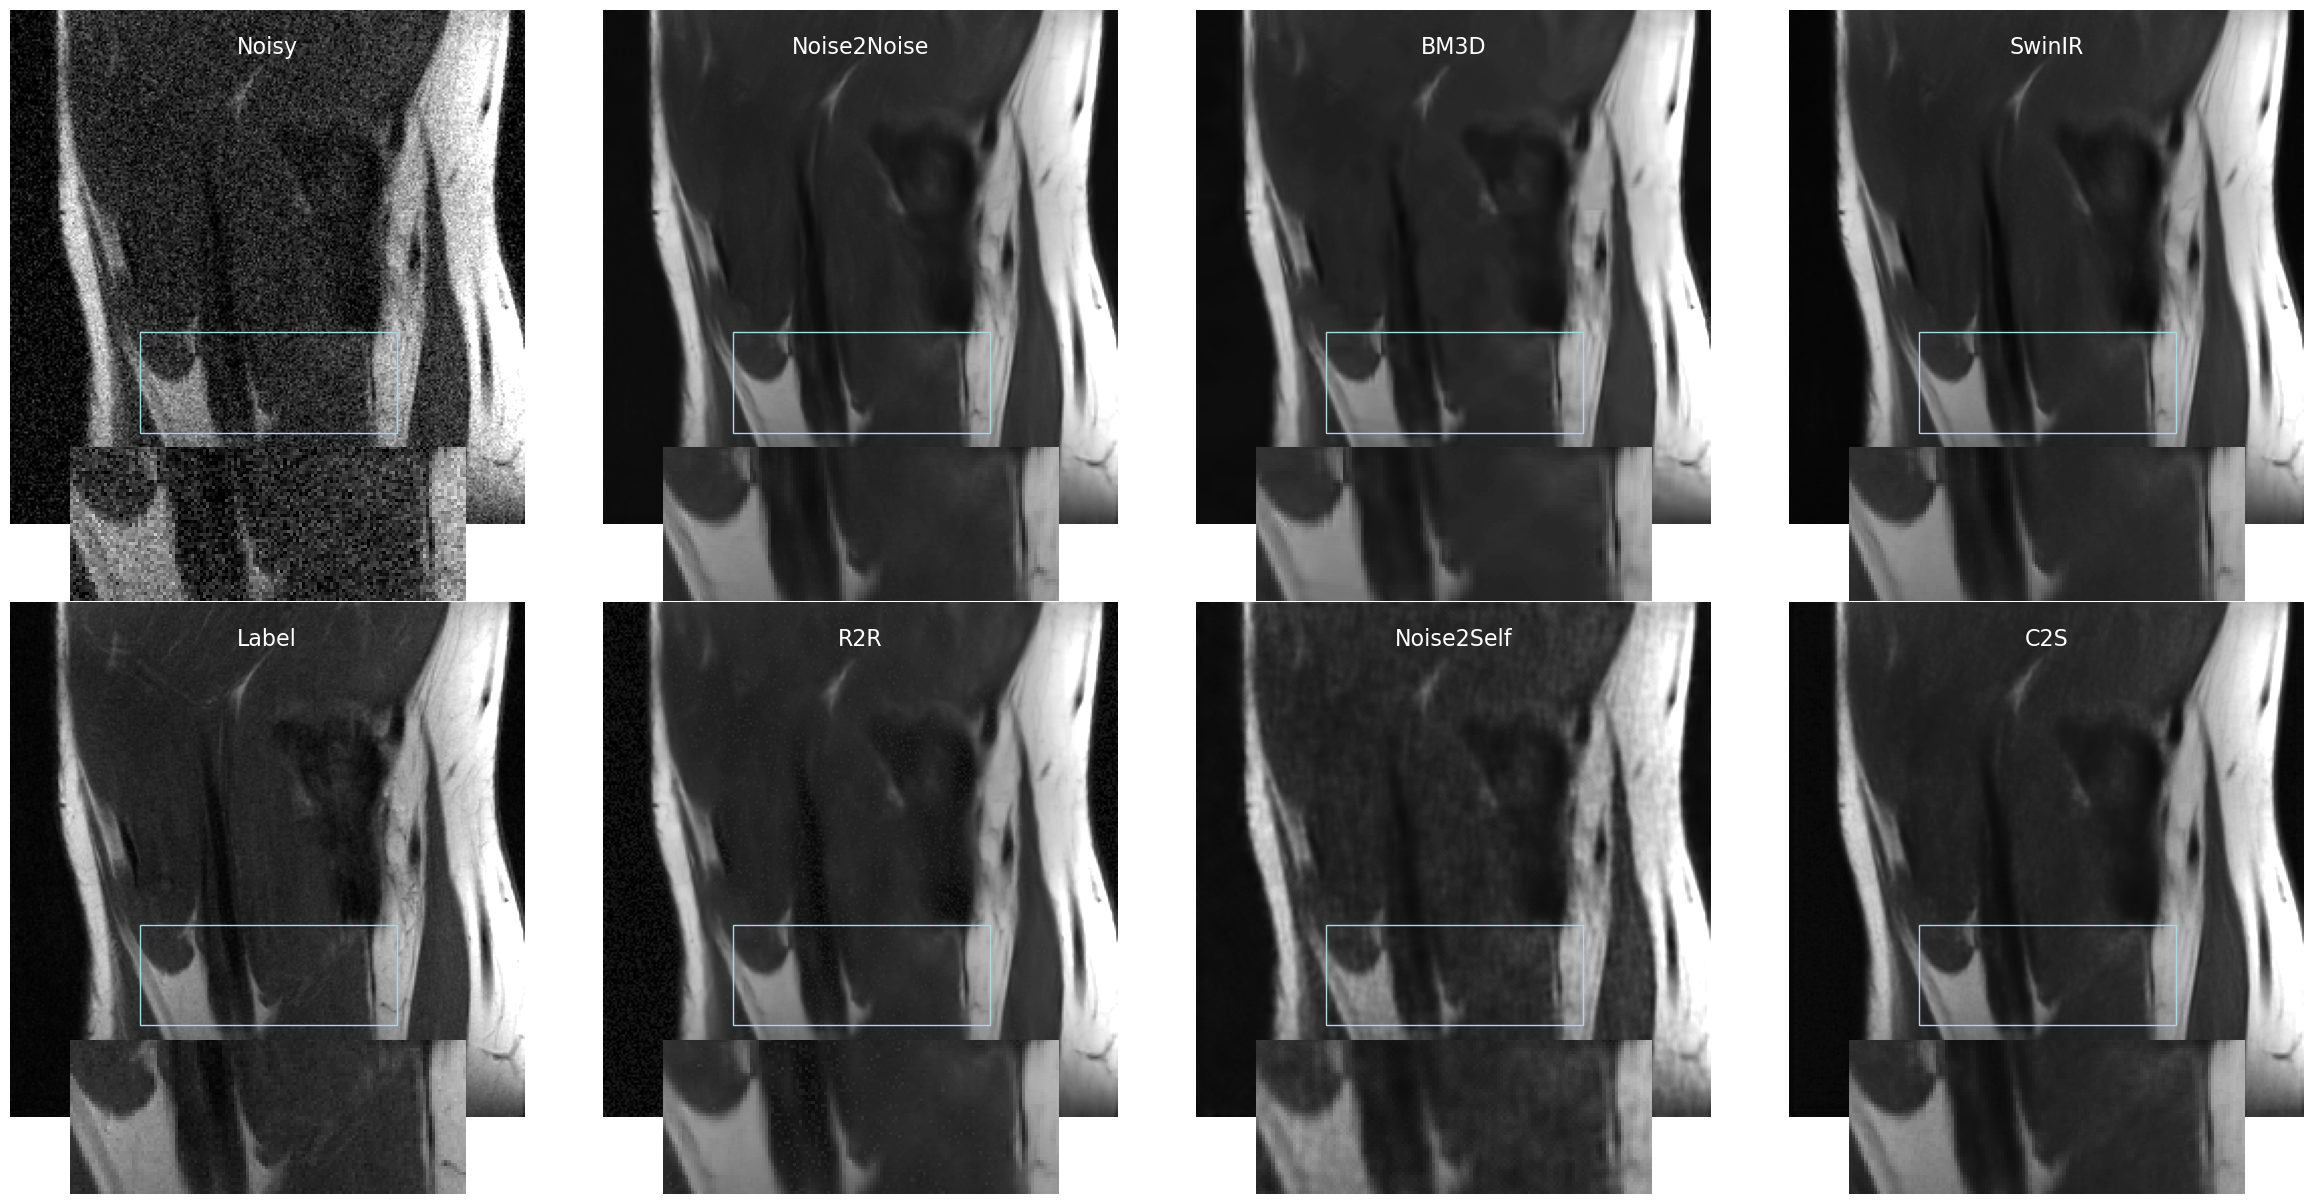

To further evaluate the robustness of C2S under different noise levels, we conducted experiments on the fastMRI dataset Zbontar et al. (2018), simulating Gaussian noise with and . As shown in Table 3, the same baseline methods are analyzed and C2S consistently achieves the best or comparable results among self-supervised methods. On PDFS with , Recorrupted2Recorrupted achieves a slightly higher PSNR (30.95 dB vs. 30.91 dB); however, C2S records the highest SSIM (0.756), indicating better detail preservation. It is worth noting that although the labels in this simulated dataset do not have added synthetic noise, they still contain inherent noise typical in MRI, albeit with higher SNR. Figure 3 demonstrates that our method balances feature preservation and noise removal, resulting in much cleaner visual representations compared to other methods. For additional results on fastMRI, refer to Appendix E.

In this section, we provide a visual comparison of several denoising methods applied to T1, T2, and FLAIR contrast images in the M4Raw dataset. The denoising methods evaluated include Noise2Noise, BM3D, SwinIR, R2R, Noise2Self, and C2S, with Multi-repetition Averaged Label serving as the ground truth reference for comparison.